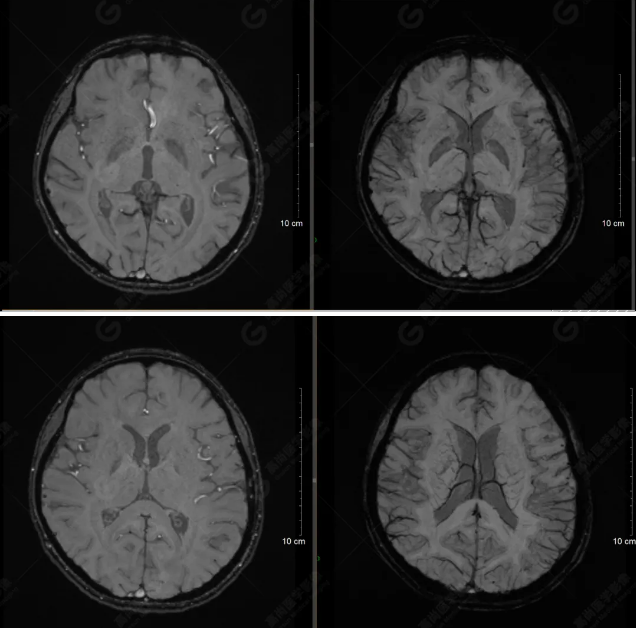

以下是平掃T2WI及FLAIR序列:

雙側(cè)大腦半球?qū)ΨQ,灰白質(zhì)對比正常,顱內(nèi)未見異常信號影。腦室系統(tǒng)未見擴(kuò)大,中線結(jié)構(gòu)居中。腦溝、裂未見增寬。幕下小腦、腦干未見異常。矢狀位示垂體形態(tài)、大小級信號未見異常。所示左側(cè)乳突內(nèi)見多發(fā)短T1長T2信號影。

顱腦MRI平掃未見明顯異常,左側(cè)乳突內(nèi)積血,建議補(bǔ)充SWI檢查。(左側(cè)為薄層原始圖像,右側(cè)為后處理5mm圖像)